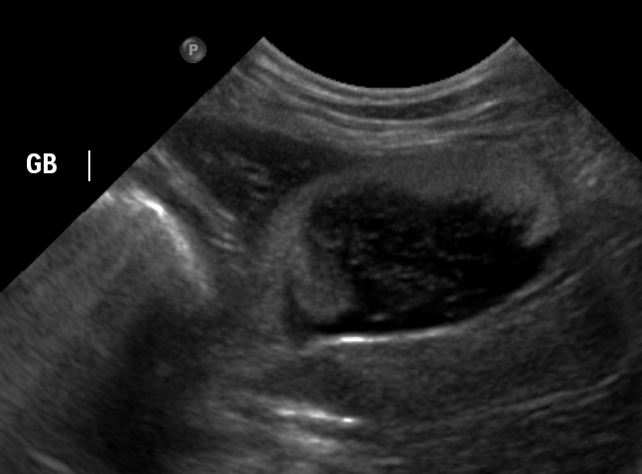

또한, 지속적인 슬러지가 확인될 경우 Gallbladder mucocele의 초기 징후일 가능성도 고려해야 하므로 정기적인 초음파 모니터링이 필요합니다.